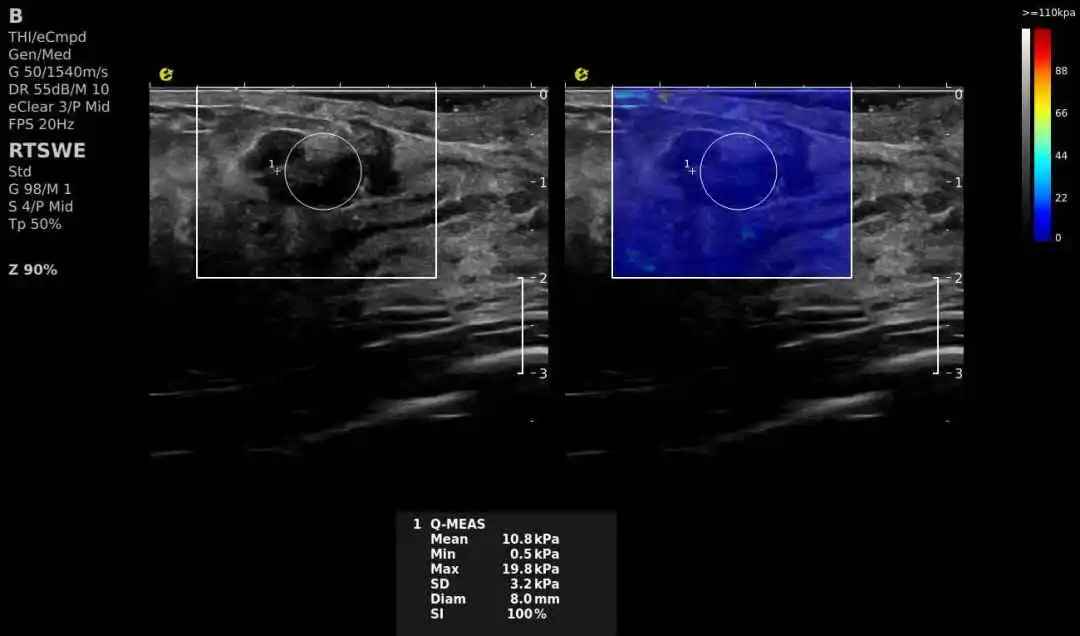

(3)量化消融范围:结合E超“组织弹性定量分析”,精准控制消融能量,既灭活肿瘤又保护正常组织!

穿34.jpg